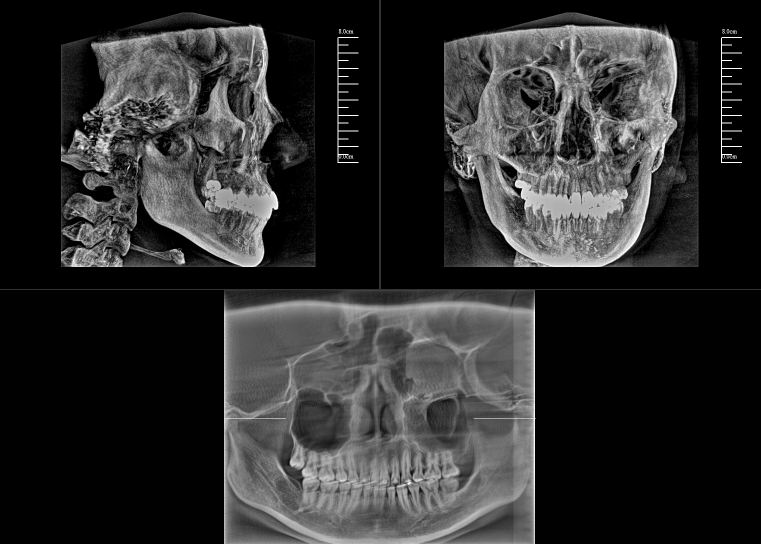

CBCT,全稱“錐束計算機斷層掃描(Cone-Beam Computed Tomography,CBCT)”,由球管和平板探測器組成。與全科CT的閉環(huán)圓孔設(shè)計不同,數(shù)字化口腔CBCT采用開放式結(jié)構(gòu)以保持其靈活性。

對于口腔內(nèi)科疾病,牙片和全景片已具有較高診斷效果;但對于牙體牙髓病,2D成像較容易發(fā)生影像重疊的情況,無法進(jìn)一步明確根管和其他周圍組織的三維信息,容易出現(xiàn)漏診或誤診根裂的情況。這就需要三維斷層成像,即數(shù)字化口腔CBCT。

數(shù)字化口腔CBCT是從三維的角度,即矢狀位、冠狀位和橫斷位來顯示病變組織和正常組織結(jié)構(gòu),有效的避免了2D圖像固有的缺陷,如正常組織器官的影像重疊,投射角度變化所致的影像扭曲、變形等,大大提高了診斷能力。

數(shù)字化口腔CBCT能在十幾秒時間內(nèi)完成患者口腔掃描,進(jìn)而生成高精度的三維影像,徹底解決了牙片機、全景機等傳統(tǒng)口腔X射線設(shè)備影像重疊、畸變的問題。可以360°全方位立體觀測牙床的骨質(zhì)密度、牙槽骨本身的高度、寬度等數(shù)據(jù),不僅能重建整個顱面區(qū)的結(jié)構(gòu),對頜面骨質(zhì)結(jié)構(gòu)進(jìn)行測量,而且還能重建精細(xì)的解剖細(xì)節(jié)。